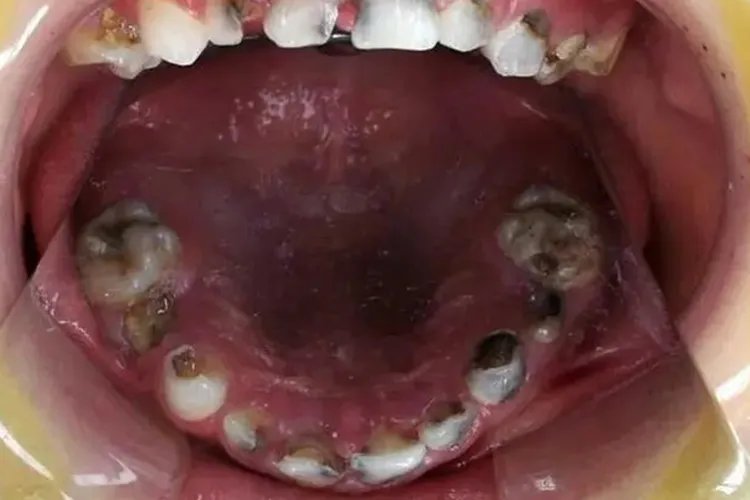

满口蛀牙图片

的有关信息介绍如下:概述满口蛀牙一般指龋病,表现为牙齿颜色、质地改变,牙齿变得敏感。满口蛀牙是口腔微生物、碳水化合物、易感性和时间四个因素相互作用的结果。症状满口蛀牙即龋病,按牙齿龋损的深度一般分为浅龋、中龋和深龋,症状表现有所差异。浅龋表现为窝沟龋的龋损部位变黑,平滑面龋一般呈白垩色、黄褐色或褐色斑点,牙齿多无洞形成,但牙齿质地发生改变,用探针检查时有粗糙感或能钩住探针尖端。此时患者一般无自觉症状,对冷、热、酸、甜刺激无明显反应。

中龋中龋患者龋损部位牙本质呈黄褐或深褐色,牙齿会有龋洞形成,牙体缺损明显,同时牙齿质地改变,病变牙本质质地较软。中龋患者对酸、甜刺激敏感,过冷、过热饮食也能产生酸痛感觉,冷刺激尤为显著,但刺激去除后症状立即消失。

深龋深龋患者龋损部位牙本质呈黄褐或深褐色,牙齿形态改变,有龋洞形成,比中龋要深,牙体缺损明显,同时会出现质地改变,病变牙本质质地较软。当食物嵌塞入龋洞中或患牙遇冷、热、酸、甜、化学刺激时可出现疼痛,去除刺激后症状立即消失。